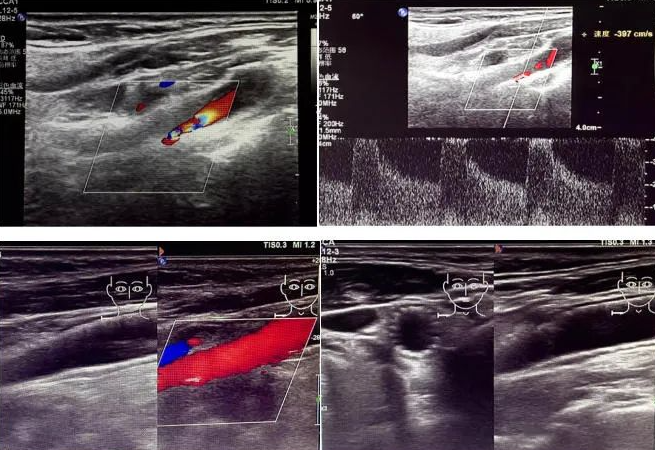

該患者因反復(fù)頭暈前來國文醫(yī)院就診。經(jīng)醫(yī)院超聲科運(yùn)用高端超聲設(shè)備進(jìn)行頸動(dòng)脈超聲檢查后發(fā)現(xiàn),其右側(cè)頸動(dòng)脈狹窄程度超過 90%。如此嚴(yán)重的狹窄狀況,猶如高速公路上的嚴(yán)重堵車,使得血液流通受阻,大大增加了腦梗死的風(fēng)險(xiǎn),時(shí)刻威脅著患者的生命安全。

頸動(dòng)脈超聲檢查作為一種無創(chuàng)、安全且準(zhǔn)確的篩查手段,在評(píng)估血管健康狀況方面發(fā)揮著重要作用。它能夠清晰地顯示血管的狹窄程度以及斑塊性質(zhì),為臨床診療提供可靠的依據(jù)。國文醫(yī)院超聲科配備的高端超聲設(shè)備,更為精準(zhǔn)診斷提供了有力支持。